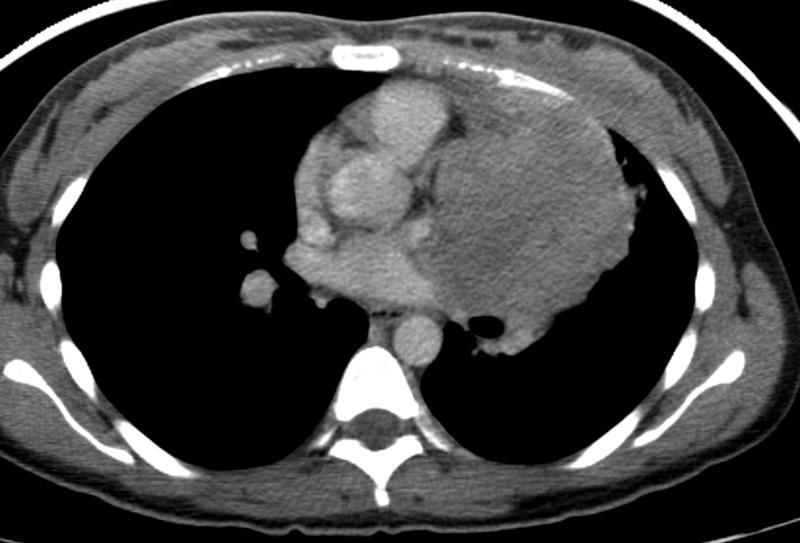

Thymic carcinoma CT